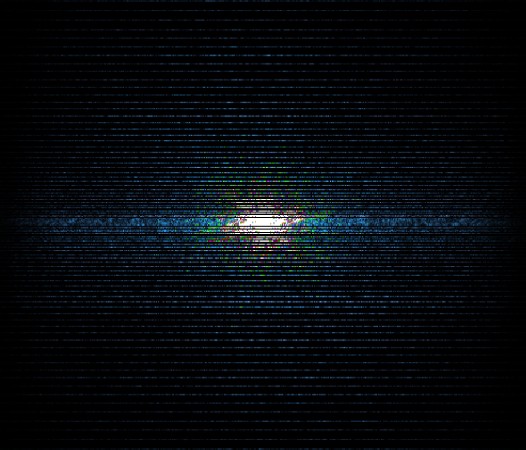

In the example below, only one fifth of the required MR radiofrequency signals is recorded. This results in a five times faster acquisition, with a subsampled k-space (top left) and inherent image artifacts after standard reconstruction (top right).

Basic compressed sensing principle

K-space compressed sense

The Compressed SENSE reconstruction then uses iterative, knowledge-based algorithms to fill in the empty lines in k-space (bottom left). This removes the artifacts while keeping the final image fully consistent with the acquired data (bottom right).